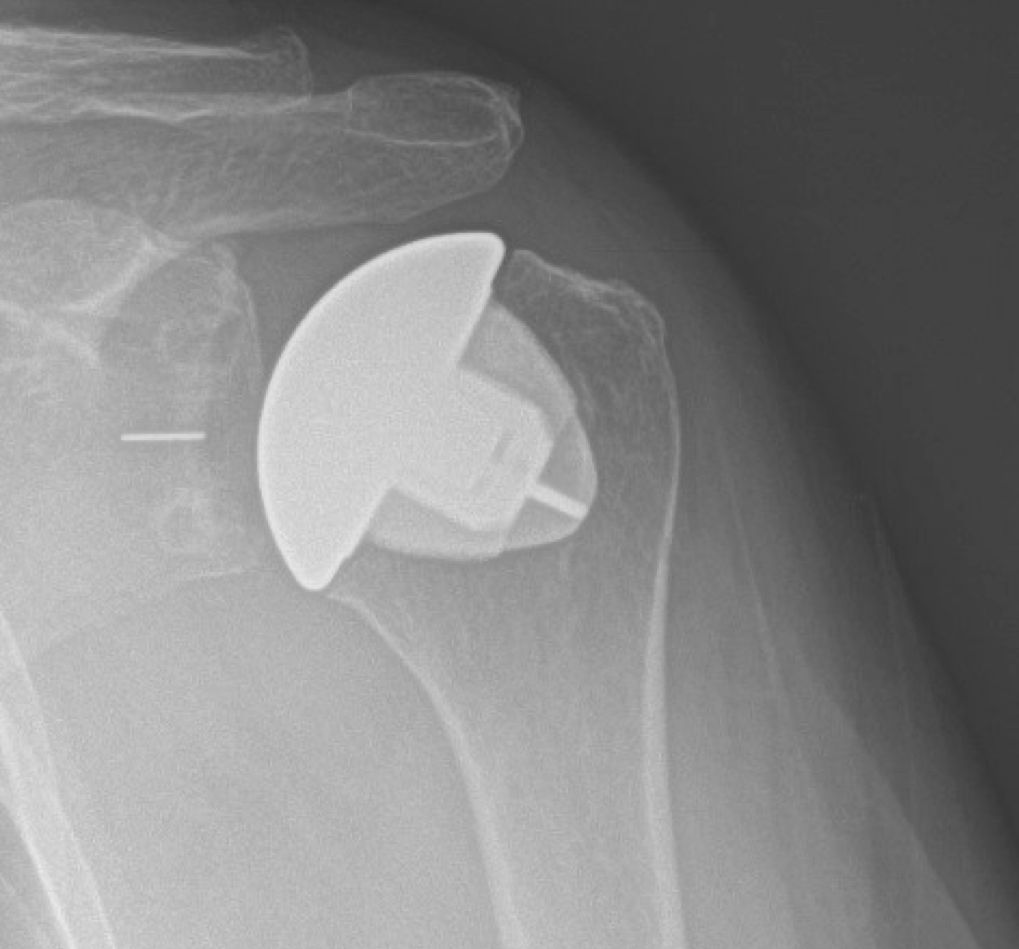

Pre-operative and post-operative xrays of a patient with rotator cuff tear arthropathy, treated with reverse total shoulder.

The reverse total shoulder was developed to help patients who have rotator cuff tears and shoulder arthritis. With a damaged rotator cuff, conventional anatomic total shoulder arthroplasty implants wear out too quickly. A reverse total shoulder involves replacing the ball and socket joints; however, the ball is moved to the "socket" side, and the "socket" is placed on the ball or humeral head side. This medializes and distalizes the center of rotation, allowing the deltoid muscle to raise the arm.

Although initially the reverse total shoulder was used for patients with shoulder arthritis with rotator cuff tears, it can also be used successfully in patients with shoulder arthritis who have significant glenoid or "socket" bone loss, complex proximal humerus fractures, chronic dislocations, revision of anatomic total shoulders, massive irreparable rotator cuff tears, and patients at high risk of developing rotator cuff tears with arthritis (advanced age, rheumatoid arthritis, etc.).